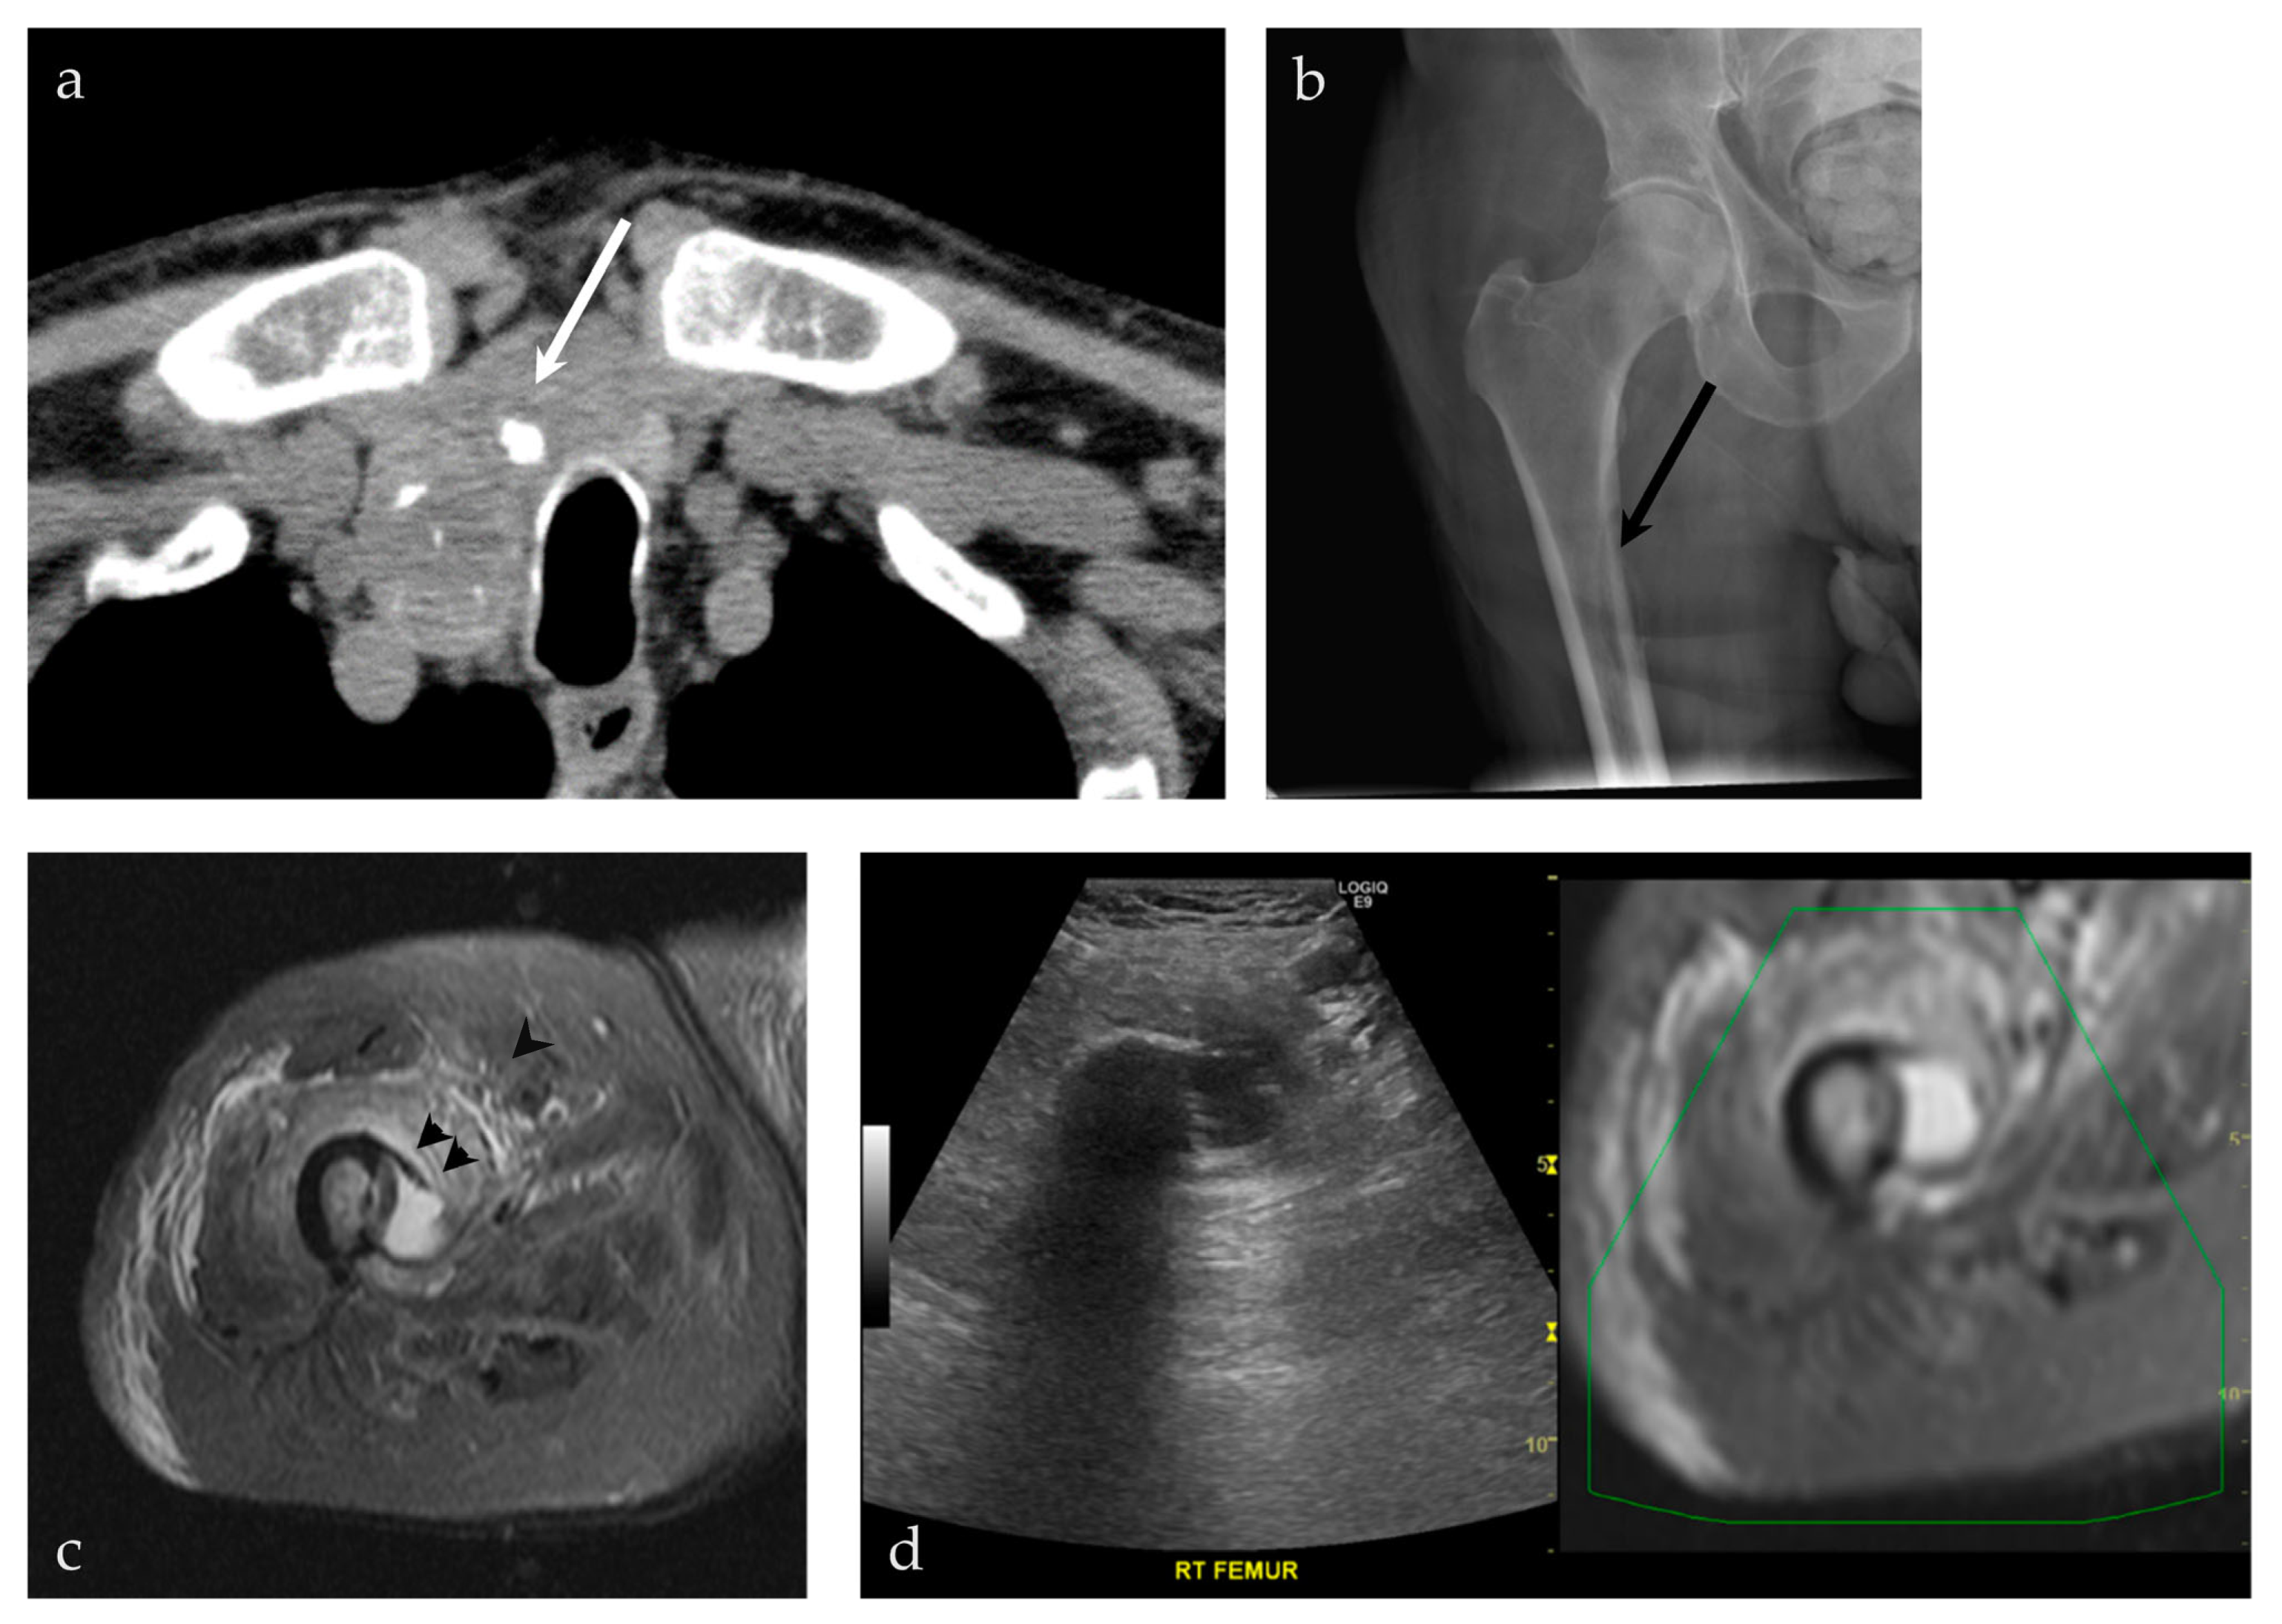

| 93/M | Right femur | US-MRI | Metastatic disease, papillary thyroid carcinoma | Neoplastic, malignant |